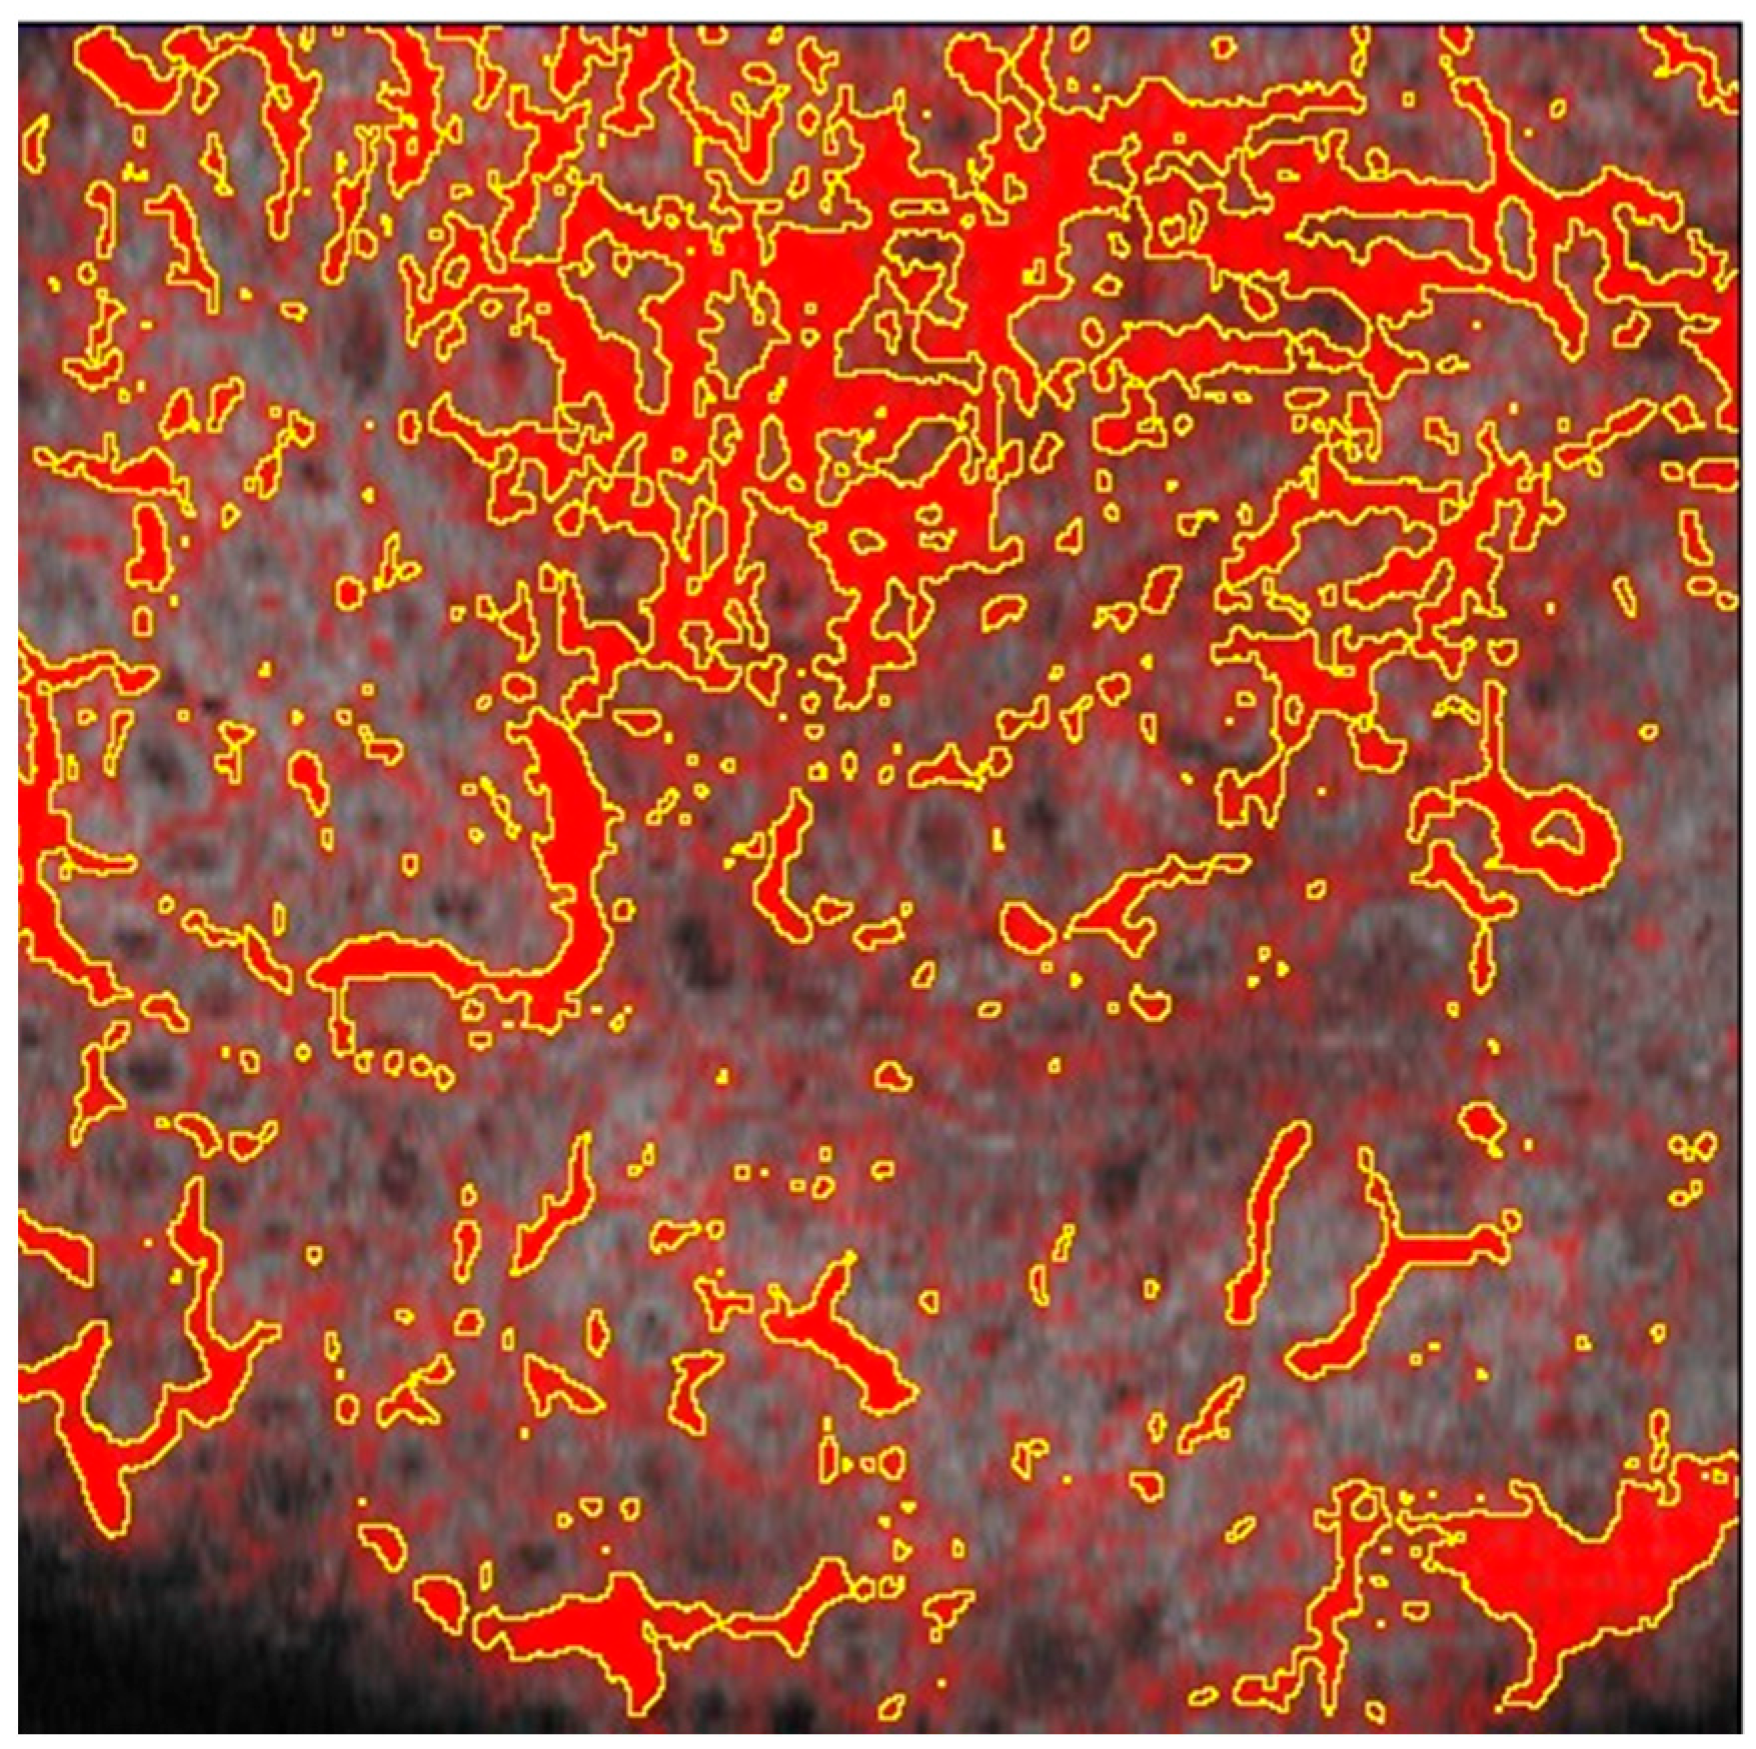

Dynamic OCT Data Analysis

- Collagen density

3.2. Collagen Density Changes

- The Collagen Density also shows a significant reduction in mean values after treatment, with a p-value of 1.66 × 10–101.66 × 10−10, confirming the treatment’s effectiveness in altering the collagen structure within the pathology site.